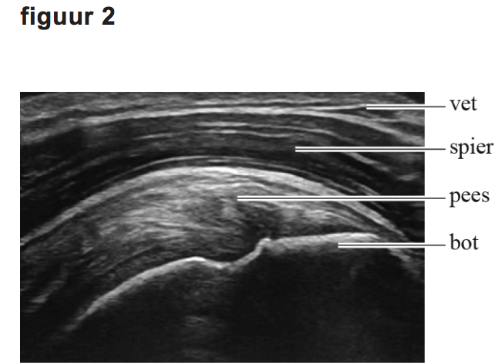

Met behulp van echografie wordt een afbeelding gemaakt van weefsel onder de huid. Zie figuur 1 en 2.